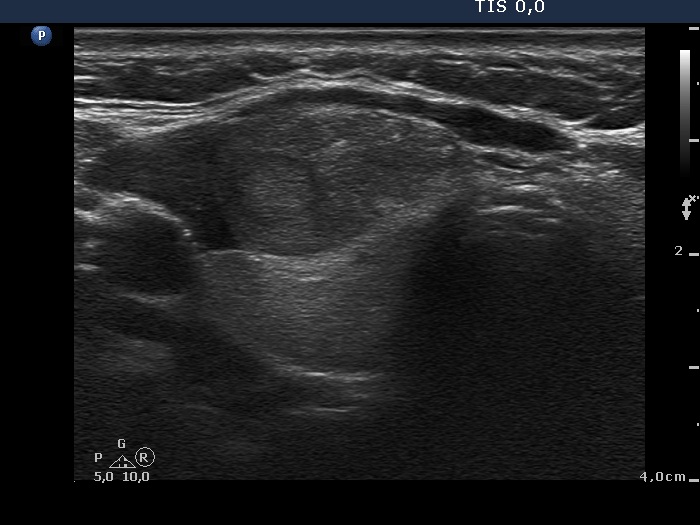

Ultrasound. The thyroid was echonormal. There was a moderately hypoechogenic mass located in the ventral surface of the right lobe. It was equivocal whether the lesion was within or outside the thyroid.

The ultrasound appearance of the lesion was unusual. We could not decide whether this lesion is within or outside the thyroid. Although more than 80% of such cases proves to be of thyroidal origin, additional tests are required to decide te issue.